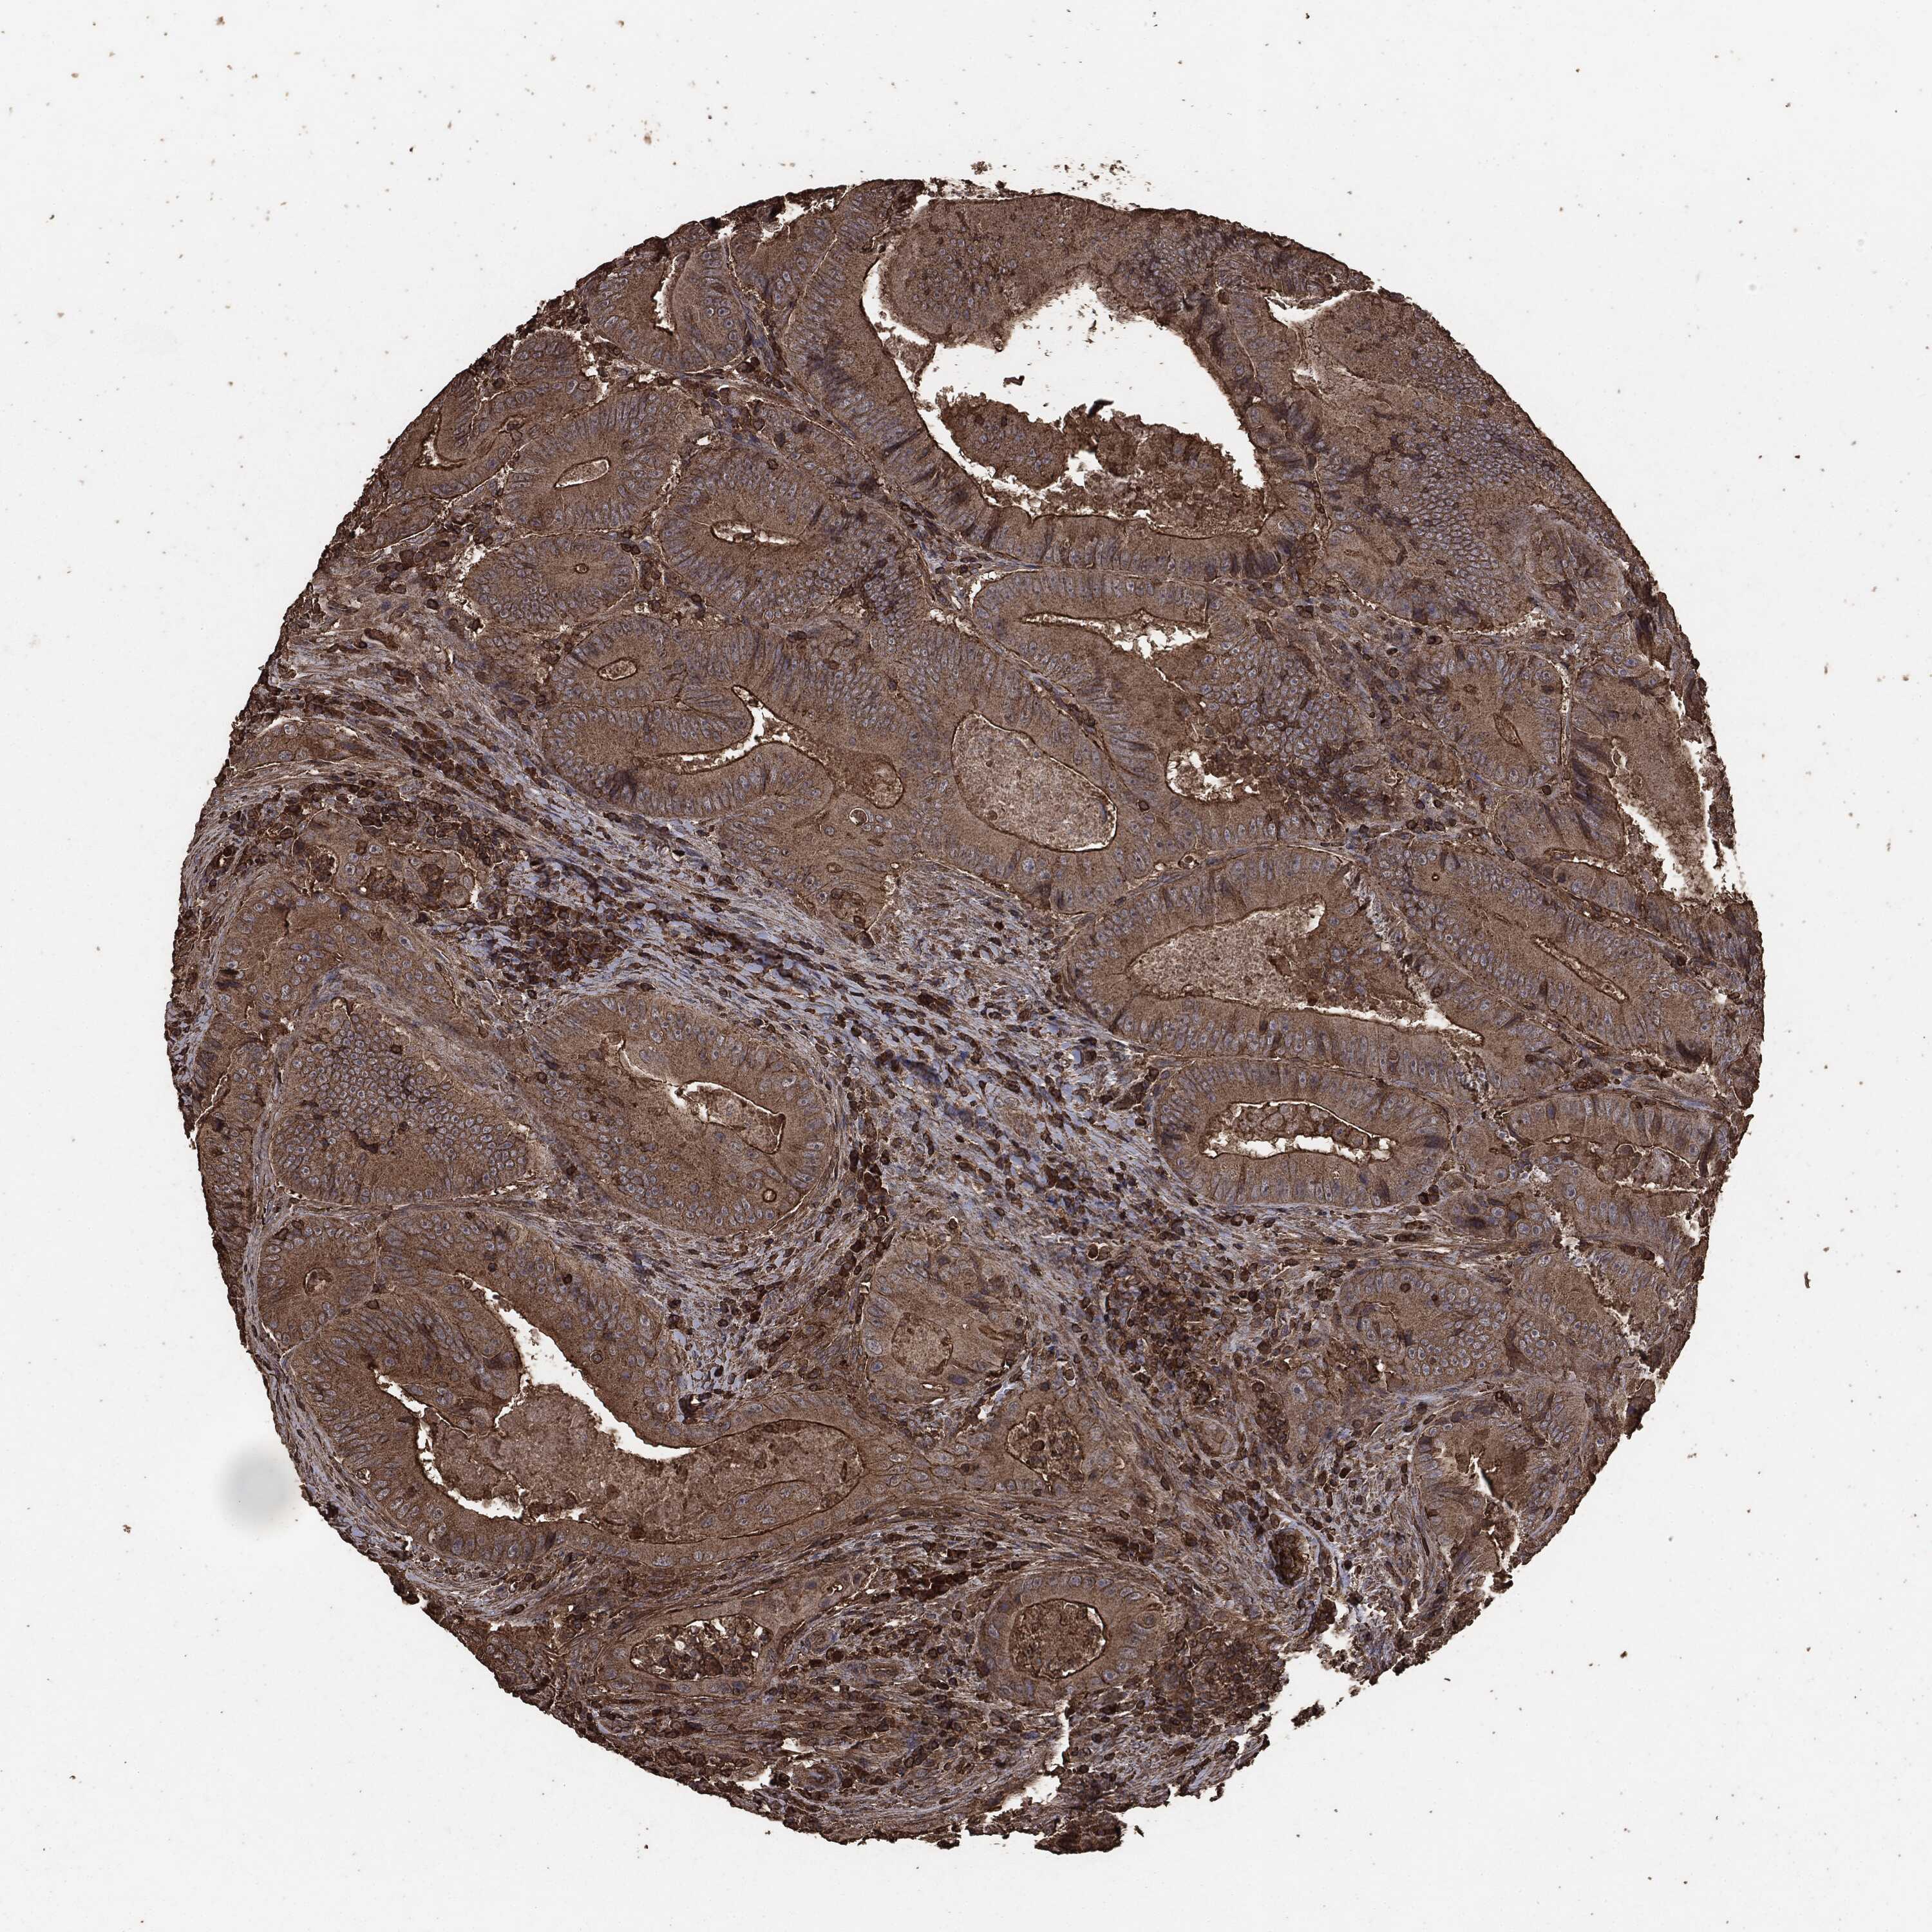

CANCER COLORECTAL CANCER Show tissue menu

ANTIBODIES

AND

VALIDATION